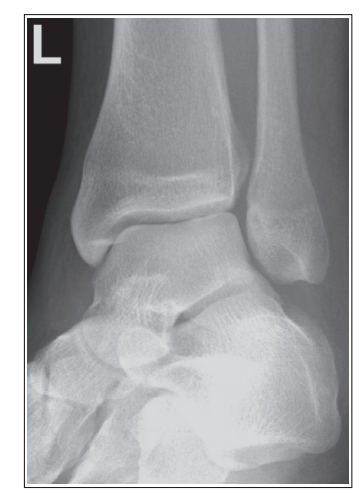

What are the issues with this mortise ankle?

the tibia superimposes less than 1/4 of the fibula, and the lateral and medial mortises are closed

Excessive obliquity/ over-rotated